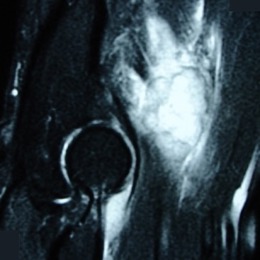

• • The work-up often consists of a physical examination, X-rays, CT scans, MRI, and sometimes bone scans are required. CT scans can be used to check for subtle mineralization that may help with the diagnosis.

Radiographic imaging is used to help form a diagnosis. These include X-Ray, MRI, CT and Bone Scans

An example of an MRI is shown.